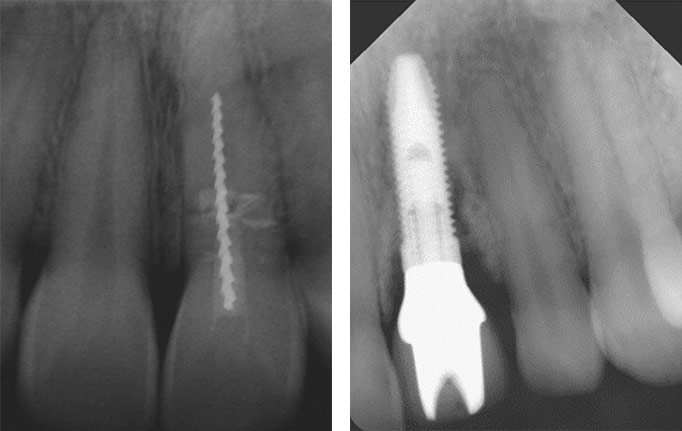

Die Knochenqualität spielt bei der Implantation die entscheidende Rolle. Ist nicht genügend feste Knochenmasse vorhanden, wird das Implantat nicht halten. Patientinnen oder Patienten, die an Osteoporose (Knochenschwund) leiden, sehen daher eine Implantation mit Sorge.

Bone Condensing: ein konisches Instrument wird vertikal so in den Knochen eingebracht, das sich die Kavernen im Knochen verdichten. Es entsteht Knochen mit kleineren Hohlräumen (rechts)

Bei Vorliegen von weichem, weniger dichtem Knochen wird zunächst nur ein kleines Loch gebohrt und das Implantat vorsichtig eingeklopft. Der Vorteil: Es wird weniger Knochenmaterial abgetragen. Der Knochen bleibt erhalten und wird verdichtet. Dieses Verfahren kann dem Implantat einen besseren Halt geben. Zusätzlich ist die Einhaltung einer längeren Einheilungszeit zu empfehlen (6 – 12 Monate im Oberkiefer).